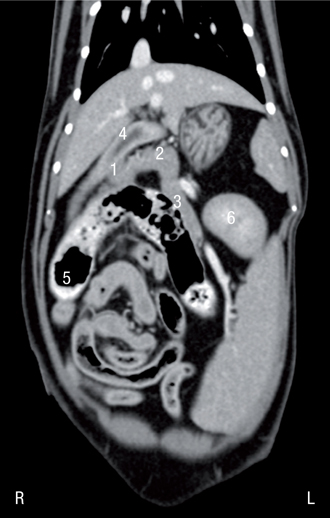

胰腺右叶位于十二指肠的肠系膜内,在降十二指肠的背内侧,右肾的腹侧,门静脉的腹外侧(图1-3.视频1)。

胰腺体部位于幽门和十二指肠的夹角内,更靠近体中线,位于右肾的前内侧以及门静脉的腹侧(图4.视频2)。猫胰腺体部与左右支之间形成的夹角比犬的小。胰腺左支起始于胰腺体部,起始部位于幽门卖的背侧尾侧。胰腺左支朝着体中线行走,位于胃的尾侧,横结肠的头侧(图5),最后到达左侧腹部,位于左肾的头侧。胃,脾和左肾头极构成的解剖位置三角区用于定位胰腺左支。胰腺左叶末端弯曲,呈钩状,延伸至脾脏。脾静脉和胰腺走向左叶平行。